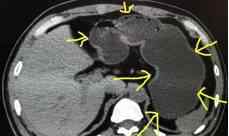

如上图1所示:黄色箭头指的是胃。这是一个不喝水的胃,没有很好的填充。我们可以看到箭头所指的胃壁明显较厚,正常的胃壁也较厚。但是如果里面藏着什么东西,胃壁上有一个小胃癌,没有办法诊断,就会导致漏诊。

再看图二:这个病人的胃肠道准备充分。我们可以看到黄色箭头所指的胃内充满了水,胃壁被填充成一层薄薄的东西。如果什么东西的胃壁长得异常增厚,一眼就能看出来。